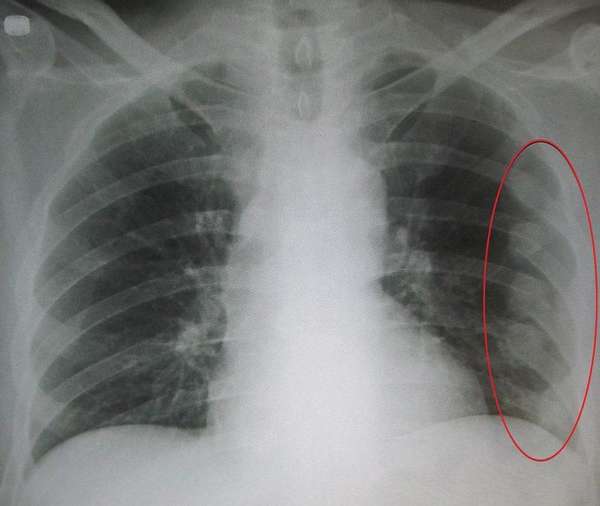

Чтобы определить трещину в ребре, необходимо провести рентгенологическое исследование. На основании снимка специалист выявляет место, где локализуется повреждение. По рентгенологическому фото врач также получает информацию о характере травмы.

При поступлении пациента с подозрением на неполный перелом ребра специалистом проводится его визуальный осмотр.

Фото снимка при переломе ребер: